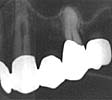

Fallbeskrivning #2

Bild 1 |

Bild 2 |

49-ĺrig kvinnlig patient, kirurgisk endodonti 23, traditionell teknik. Perforation juxtaraadikulärt (bild 1). Marginal kommunikation till destrukuktionen förelĺg vilket konstaterades preoperativt. |

Ett ĺr efter ingreppet föreligger avslutad läkning, ingen kvarstĺende ficka (bild 2). Luxalloy användes som retrogradt fyllningsmaterial.